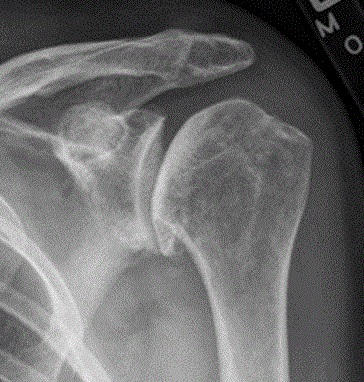

어깨의 뼈 골절은 어깨의 세 뼈, 즉 쇄골, 견갑골, 상완골 중 하나에 부분적 또는 전체적으로 금이 가는 것을 포함한다. 뼈 골절은 일반적으로 낙상이나 어깨에 가해지는 타격과 같은 충격 부상의 결과로 발생한다. 골절은 대개 쇄골이나 상완골의 목(머리 아래 부위)을 포함한다. 견갑골 골절은 때때로 오훼돌기를 통해 발생한다.심각한 부상 후 발생하는 어깨 골절은 일반적으로 심한 통증을 동반한다. 짧은 시간 안에 해당 부위 주변에 발적과 멍이 생길 수 있다. 때로는 뼈가 제 위치에서 벗어난 것처럼 보이기 때문에 골절이 명확하게 드러나기도 한다. (그러나 이는 관련 없는 탈구 및 분리에서도 발생한다.) 진단과 심각성은 X-레이 촬영으로 확인할 수 있다.

어깨 관절염은 통증, 운동 범위 감소 및 어깨 사용의 어려움을 유발한다. 어깨 엑스레이는 볼과 소켓 사이의 정상적인 공간 손실을 보여준다. 엑스레이는 어깨 골관절염의 방사선학적 단계를 제공할 수 있다.